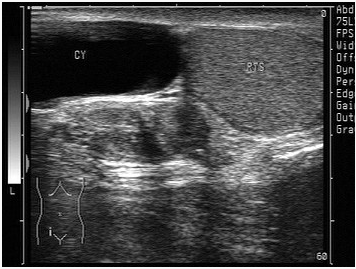

临床资料:男,56岁,黑人(赞比亚)。自诉阴囊肿胀不适20年余。超声综合描述:左侧睾丸足侧外可见4.3cm×2.7cm无回声区,形态不规则,内见完整及不完整分隔,透声清亮,包膜完整。

超声提示()

A:左阴囊内血肿

B:左侧睾丸鞘膜积液

C:左侧睾丸囊肿

D:左侧附睾旁囊肿